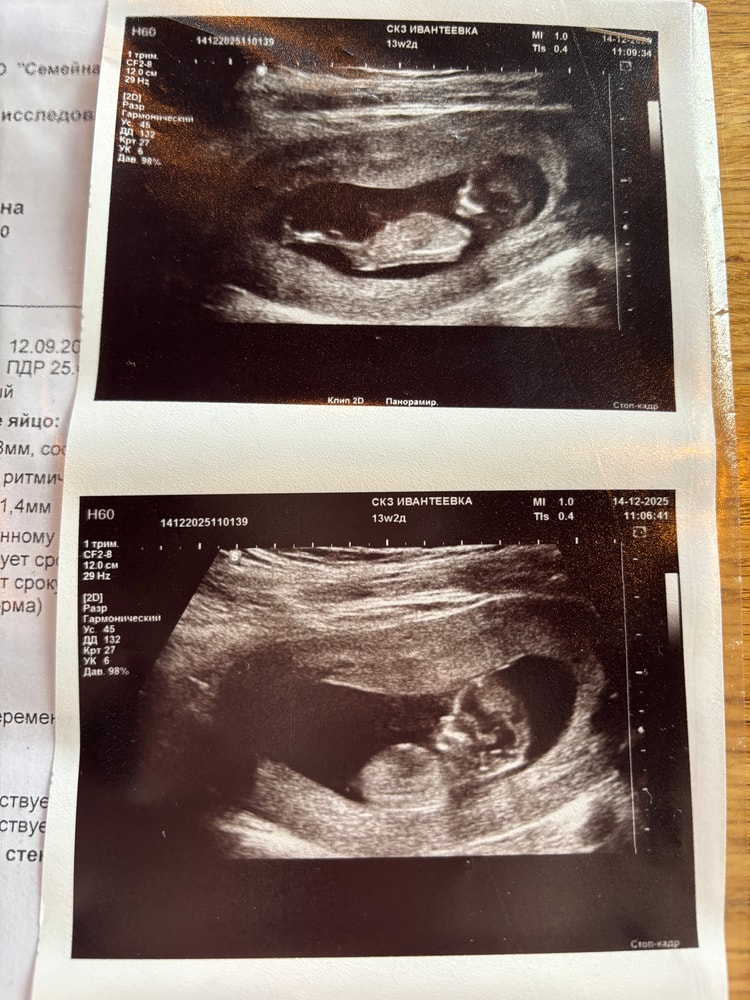

1 скрининг прошел удачно, чему я очень и очень рада, безумно переживала , поскольку болела весь первый триместр. Врач сказала, что похоже на девочку, а вы как думаете?))